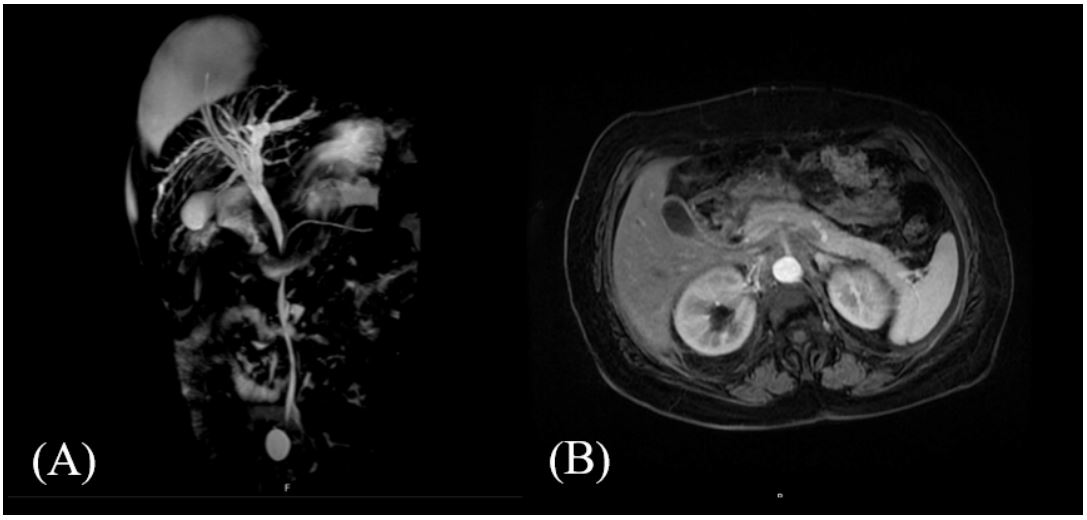

In November 2021 the patient performed a MRCP that exhibited very suggestive radiological signs of microlithiasis of the gallbladder with no intra and extrahepatic bile ducts described as normal and without dilation of the biliary system. The liver and the pancreas were also described as normal.

Figure 1: (A) Coronal section of a MRCP that shows the biliary tree. (B) Axial section of a MRCP in which we can see the gallbladder with suggestive radiological signs of microlithiasis.